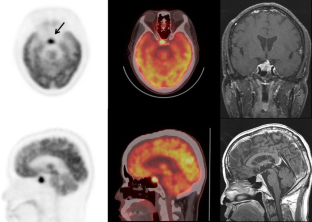

Fig. 1

Fig. 2

Fig. 3

Focally increased pituitary FDG uptake on PET/CT was found in 30 of 40,967 patients, accounting for an incidence of 0.073%. The mean SUVmax of 30 patients was 8.9 ± 6.6 (range: 3.2–32.6). Histological diagnosis was obtained in three patients and included two growth hormone-secreting adenomas and one non-functioning adenoma. Hormone assays were performed on serum samples from 11 patients, 2 of whom were shown to have hypersecretion of pituitary hormone. MRI was performed on 19 patients. Abnormal MRI findings suggesting a pituitary mass were found in 18 of 19 cases (94.7%). The mean SUVmax calculated without correction for partial volume effect for macroadenomas was significantly higher than the SUVmax for microadenomas (11.5 ± 8.4 vs 4.8 ± 1.3; p < 0.05). There were no cases diagnosed with metastasis to the pituitary gland during clinical follow-up.